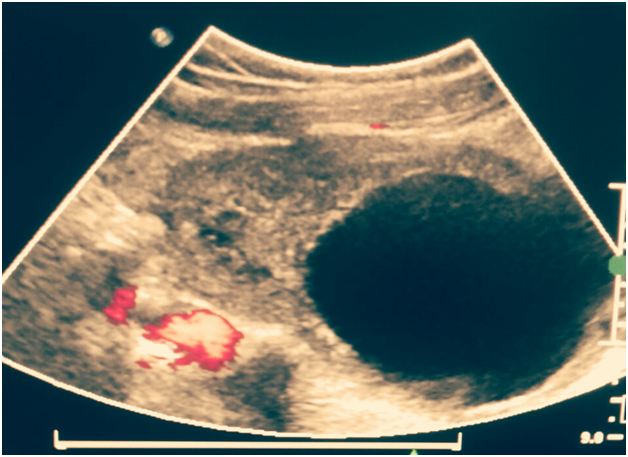

Intraoperatively, right adnexa was twisted for three and half turns on its pedicle and appeared bluish black, edematous and congested suggestive of haemorrhagic necrosis. Following detorsion, right tube immediately gained colour and the right ovary also began to regain its colour slowly in the periphery. On attempting cystectomy, cyst ruptured and drained hemorrhagic fluid, the surrounding ovarian tissue was highly edematous and friable. Cystectomy was done with removal of the surrounding blackish and friable tissue. Rest of the ovary near the hilum was preserved despite, it appearing bluish-black and edematous. Left ovary was enlarged with multiple small follicles and a 3x2 cm haemorrhagic cyst was found which was also excised. Post operative period was uneventful and the patient was discharged the next day with a 5 day course of antibiotics and analgesics. A follow up scan was done after 6 weeks which revealed remnant ovarian tissue on the right side along with good follicular activity and normal blood flow (Figures 1-3).

Figure 3 Follow up scan revealed follicular activity in remnant ovary.

In the presented case also, part of the necrotic looking ovary was left in situ with removal of the cyst and surrounding friable ovarian tissue, follow up scan after 6 weeks revealed good blood flow in the remnant ovary along with follicular activity. To conclude, authors stress on the role of strong clinical suspicion of ovarian torsion despite normal Doppler findings especially, in young girls to prevent irreversible damage to the ovary. Clinical appearance of the torsed adnexa does not correlate well with the likelihood of residual ovarian function and recovery and hence every possible effort should be made to reestablish the blood supply by detorsion and doing an adnexa sparing surgery. Laparoscopic approach with its inherent advantages of shorter hospital stay and quick post operative recovery must now be accepted as the cornerstone of managing such emergencies and conservative therapy should be offered in order to safeguard future fertility in young girls presenting with ovarian torsion.